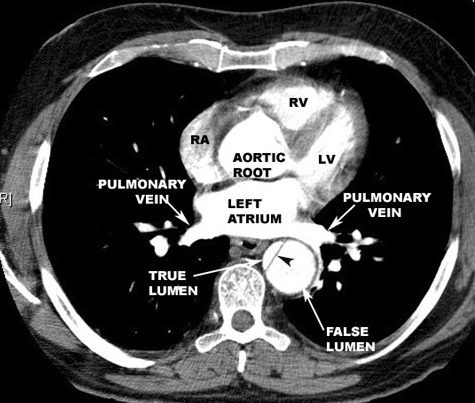

Aortic Dissection CT

Dissection Aorta CT

• Arrowheads: Intimal flap

Radiologic Criteria for Dissection in CT scanning:

• The diagnosis of aortic dissection by CT requires the identification of two distinct lumens with a visible intimal flap:

• False lumen

• Flap

• True lumen

• Indirect signs include compression of the true lumen by the false lumen, spiraling of a thrombosed false lumen, displaced intimal calcification, widening of the aortic lumen, and ulcer-like projections of contrast material.

• The advantages of CT include ready availability and the fact that it is a noninvasive procedure.

• It is also helpful in identifying causes of aortic widening other than dissection (such as tumors or periaortic hematomas), and can identify the presence of a pericardial effusion.

• It is disadvantageous in that it cannot identify the presence of aortic insufficiency or delineate coronary arteries.

• Contrast-enhancing CT scanning has a reported sensitivity of 94%, but a specificity of only 87%.

• Current CT scanning techniques improve the accuracy of CT scanning in diagnosing aortic dissection.

• 3D reconstructed images provide remarkable details.